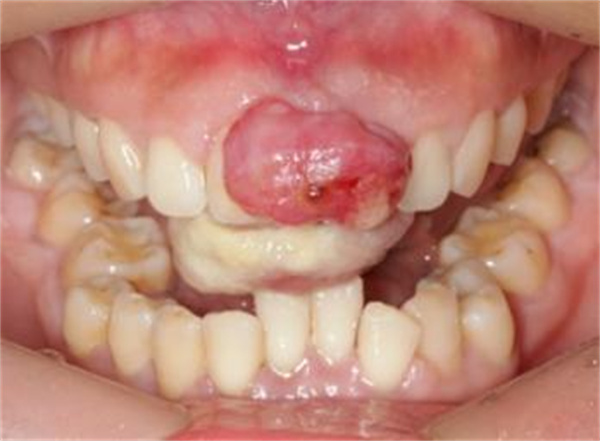

“熊猫er牙医,我刚开始也出血,后面牙龈上长了个小包,我没当回事。几周就成鹌鹑蛋那么大,我说话要咬到它,吃饭也要咬到它,一咬到就出血,要流好久才止得住,好吓人哟。”

“这是典型的妊娠期龈瘤,特点是易出血和长得飞快。?由于妊娠期龈炎未得到及时治疗,增生的牙龈发展为化脓性肉芽肿,即妊娠期龈瘤。严重妨碍准妈妈们进食,甚至会导致感染和贫血。由于瘤体生长速度快,如不及时治疗还会引起牙齿松动脱落。因此,一旦出现类似情况,应及时就诊。”